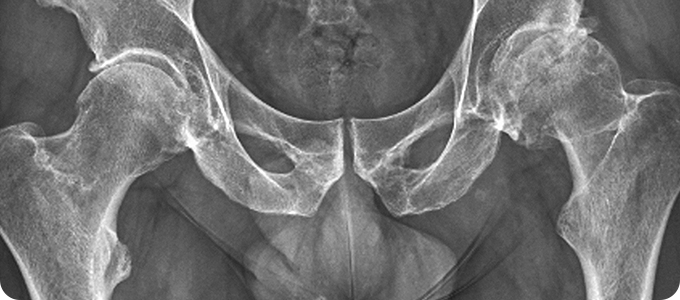

고관절골절

부분치환술 관련 이미지

• 허벅지 뼈와 골반의 연결 부분인 고관절에 금이 가거나 부러지는 것입니다.

골절이 발생하면 환자의 움직임이 제한되어 대부분의 시간을 누워 있게 되므로

욕창, 폐렴, 뇌졸중, 심근 경색, 인지 능력 저하 등의 합병증이 나타날 수 있습니다.

• 대부분 넘어지면서 고관절부의 외측을 직접 부딪히면서 발생합니다.

젊은 연령에서는 추락이나 교통사고 같은 고에너지 외상에 의한 것이 대부분입니다.

노인들은 골다공증으로 인해 가벼운 낙상에 의해서도 뼈가 부러질 수 있습니다.

• 골절 후 즉시 허벅지 바깥쪽과 사타구니에 심한 통증이 있습니다.

다리를 움직일 수 없습니다. 고관절을 움직일 경우 더욱 심한 통증이 나타납니다.

골절된 쪽의 다리가 반대쪽에 비해 짧아지며, 발과 무릎이 바깥쪽으로 돌아가있습니다.